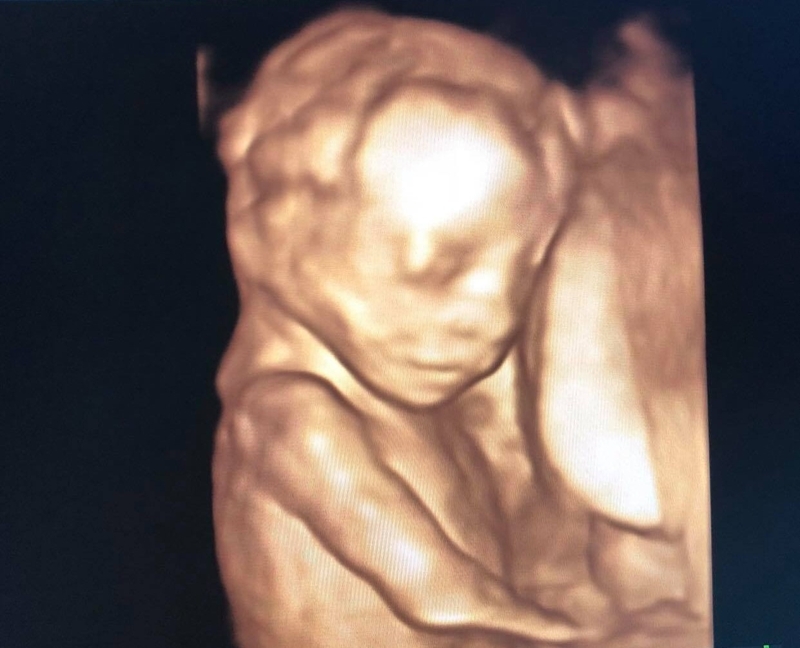

Siêu âm thai nhi 19 tuần tuổi cho thấy gì?

Siêu âm thai nhi 19 tuần tuổi là cột mốc để bác sĩ kiểm tra các tình trạng của thai nhi có bình thường hay không. Từ đó có thể đưa ra những lời khuyên thích hợp cho mẹ bầu giúp thai nhi phát triển khoẻ mạnh.

Khi thai nhi bước sang tuần thứ 19 cũng là lúc mẹ bầu đi được một nửa quãng đường thai nghén. Việc thực hiện siêu âm thai nhi 19 tuần tuổi là rất quan trọng. Mẹ bầu cần lưu ý để tránh bỏ lỡ thời điểm này.

Siêu âm thai nhi 19 tuần tuổi cho thấy gì? 1 Siêu âm định kỳ rất quan trọng đối với mẹ bầu

Siêu âm thai nhi 19 tuần tuổi cho thấy gì? 2 Thai nhi bắt đầu chuyển động trong bụng mẹ